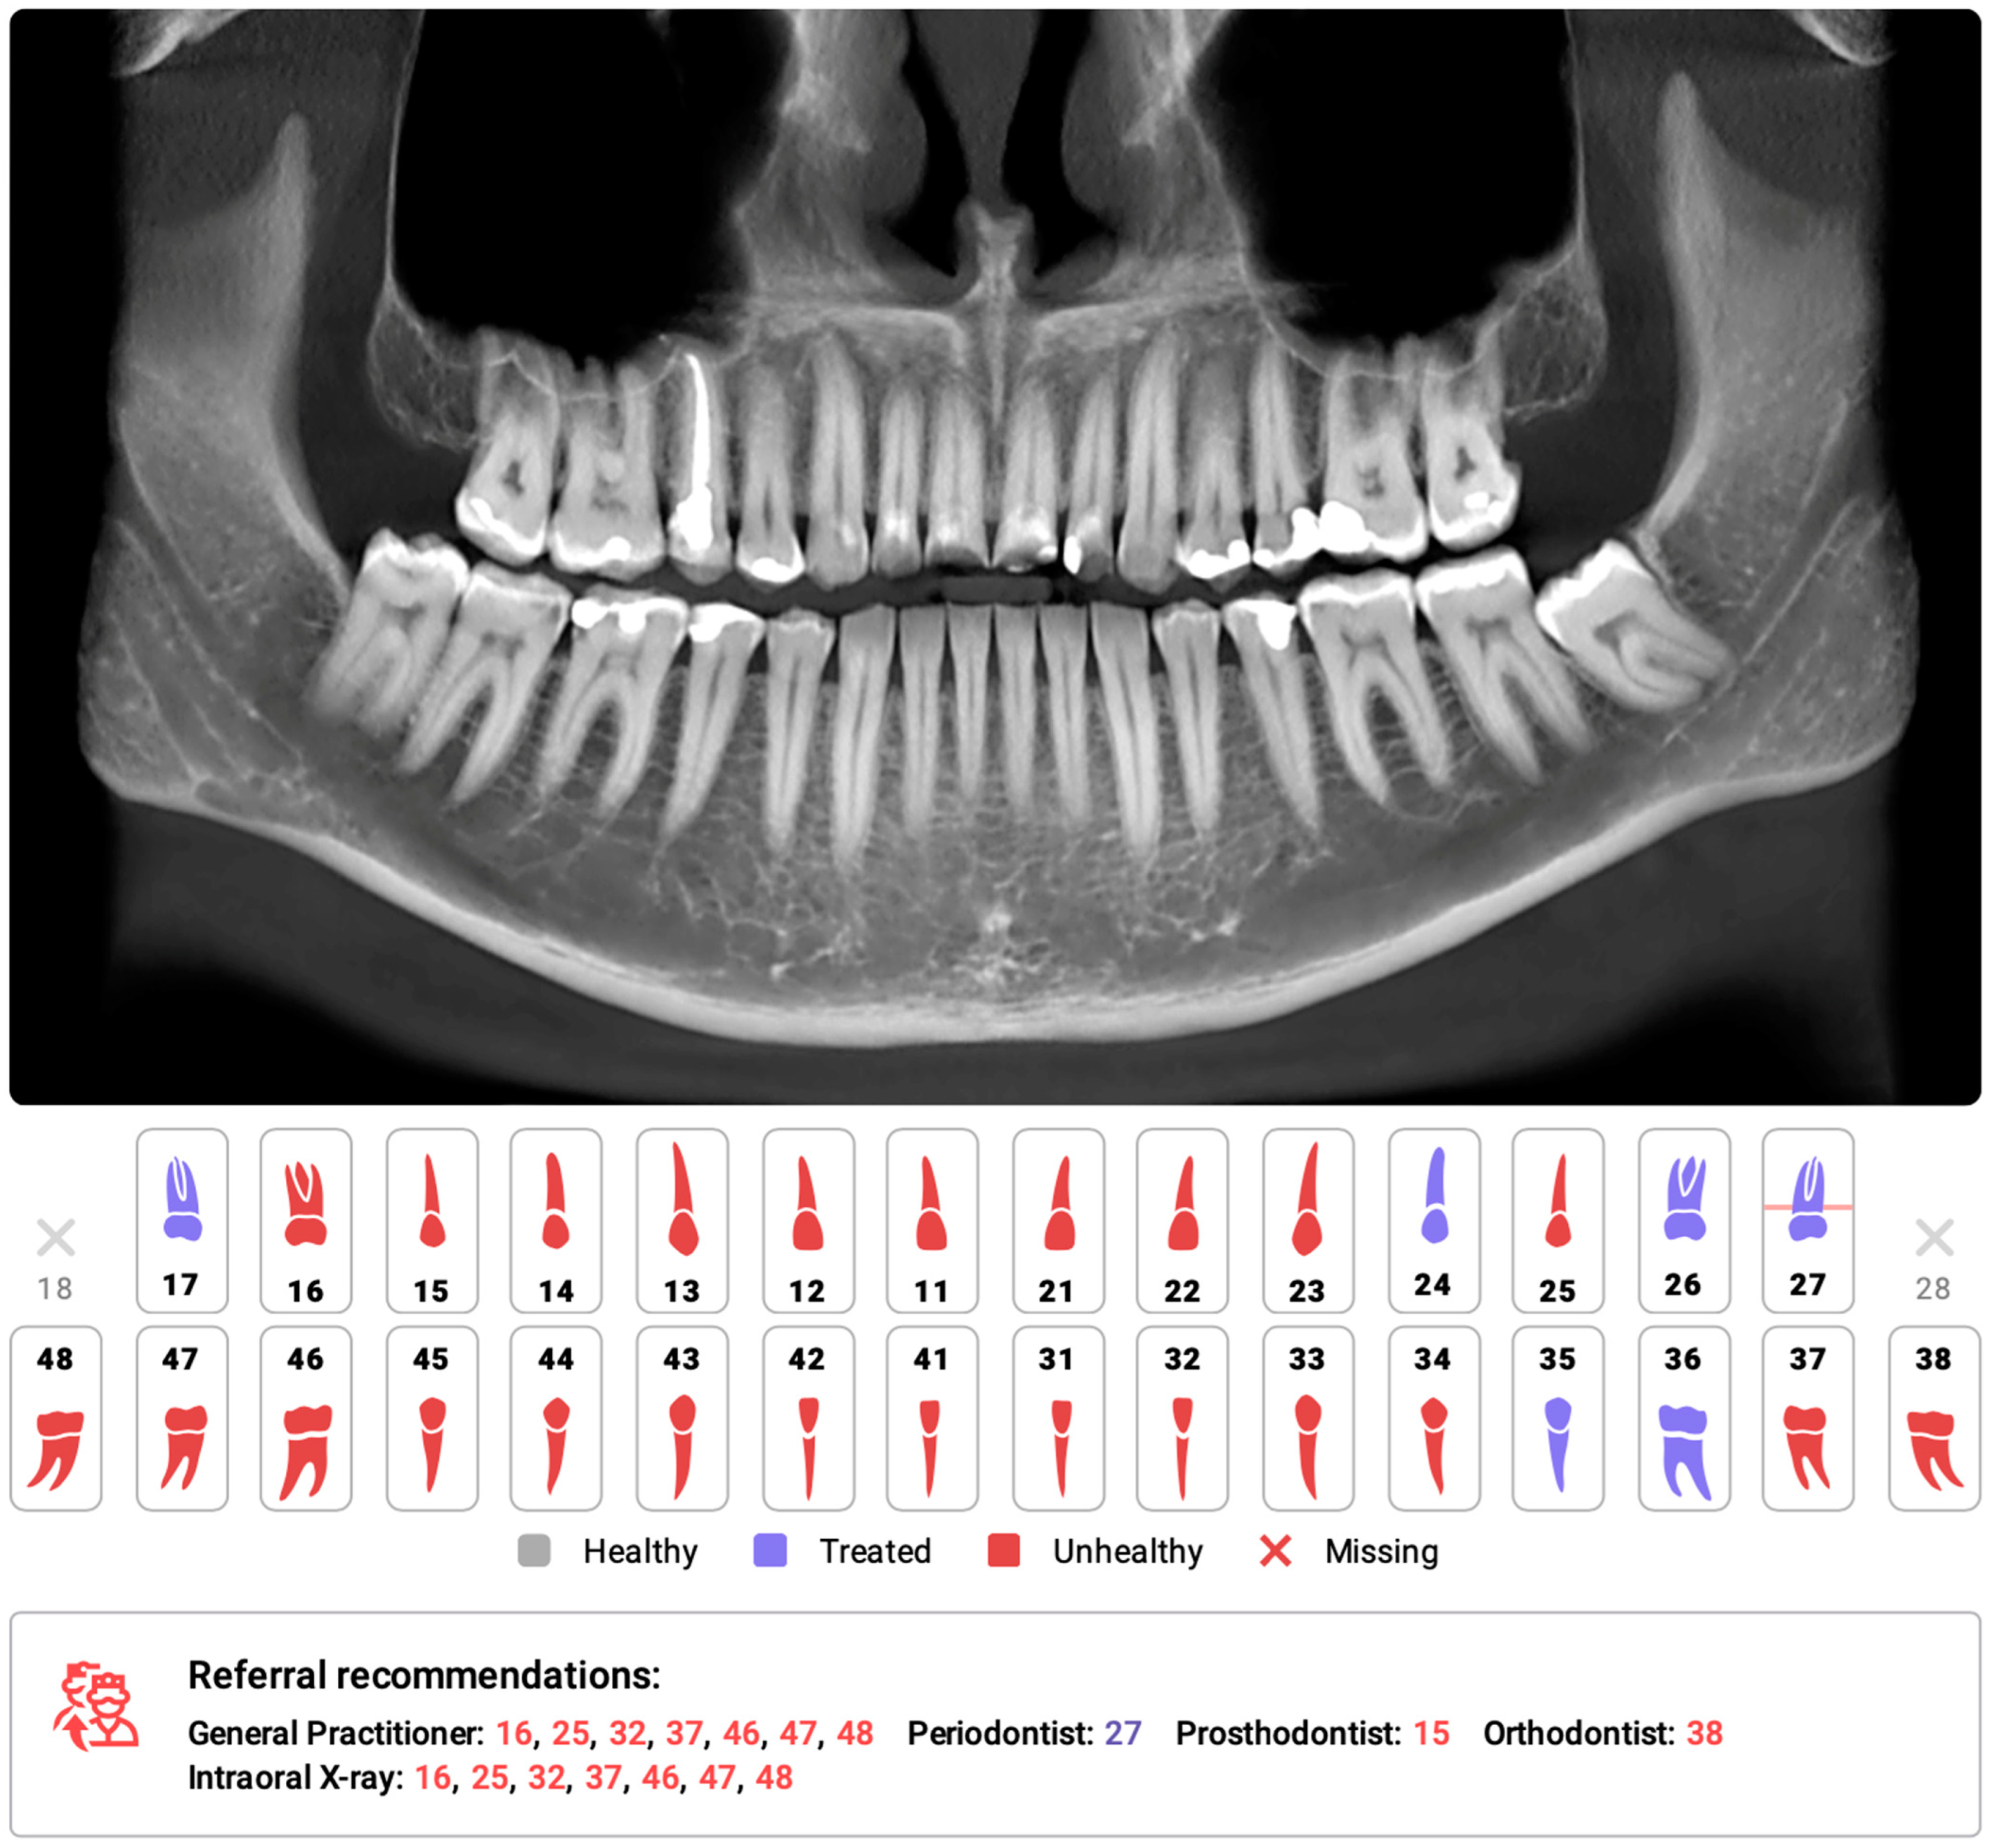

3.2.1. Dental Diagnostics